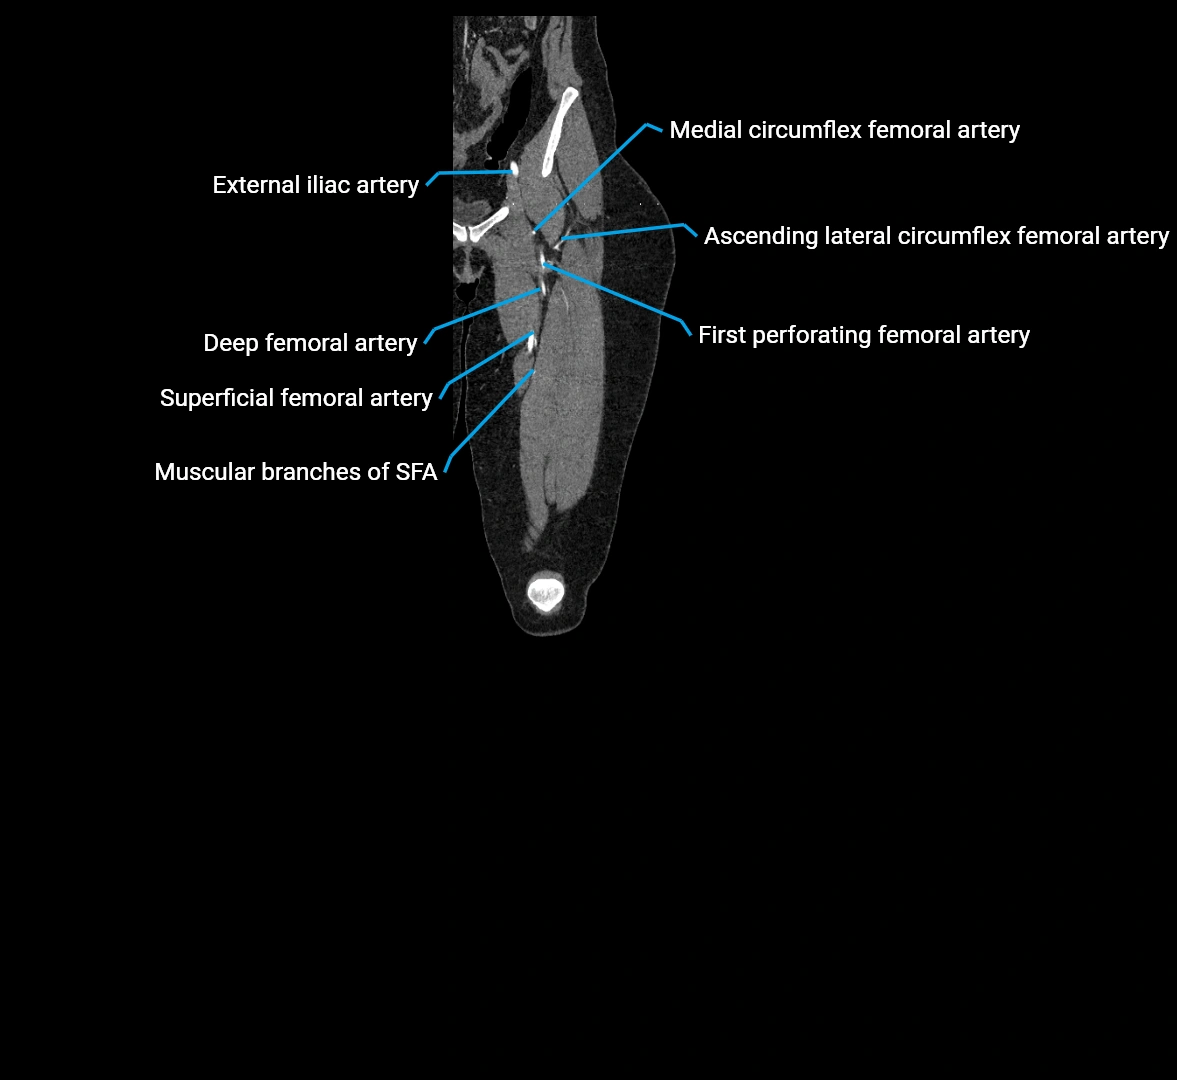

Contrast-enhanced CT (CTA):

• Gold standard for abdominal aortic imaging

• Provides excellent detail of lumen, wall, aneurysm, thrombus, and branch vessels

• Multiplanar and 3D reconstructions help in aneurysm measurement, stent graft planning, and dissection evaluation